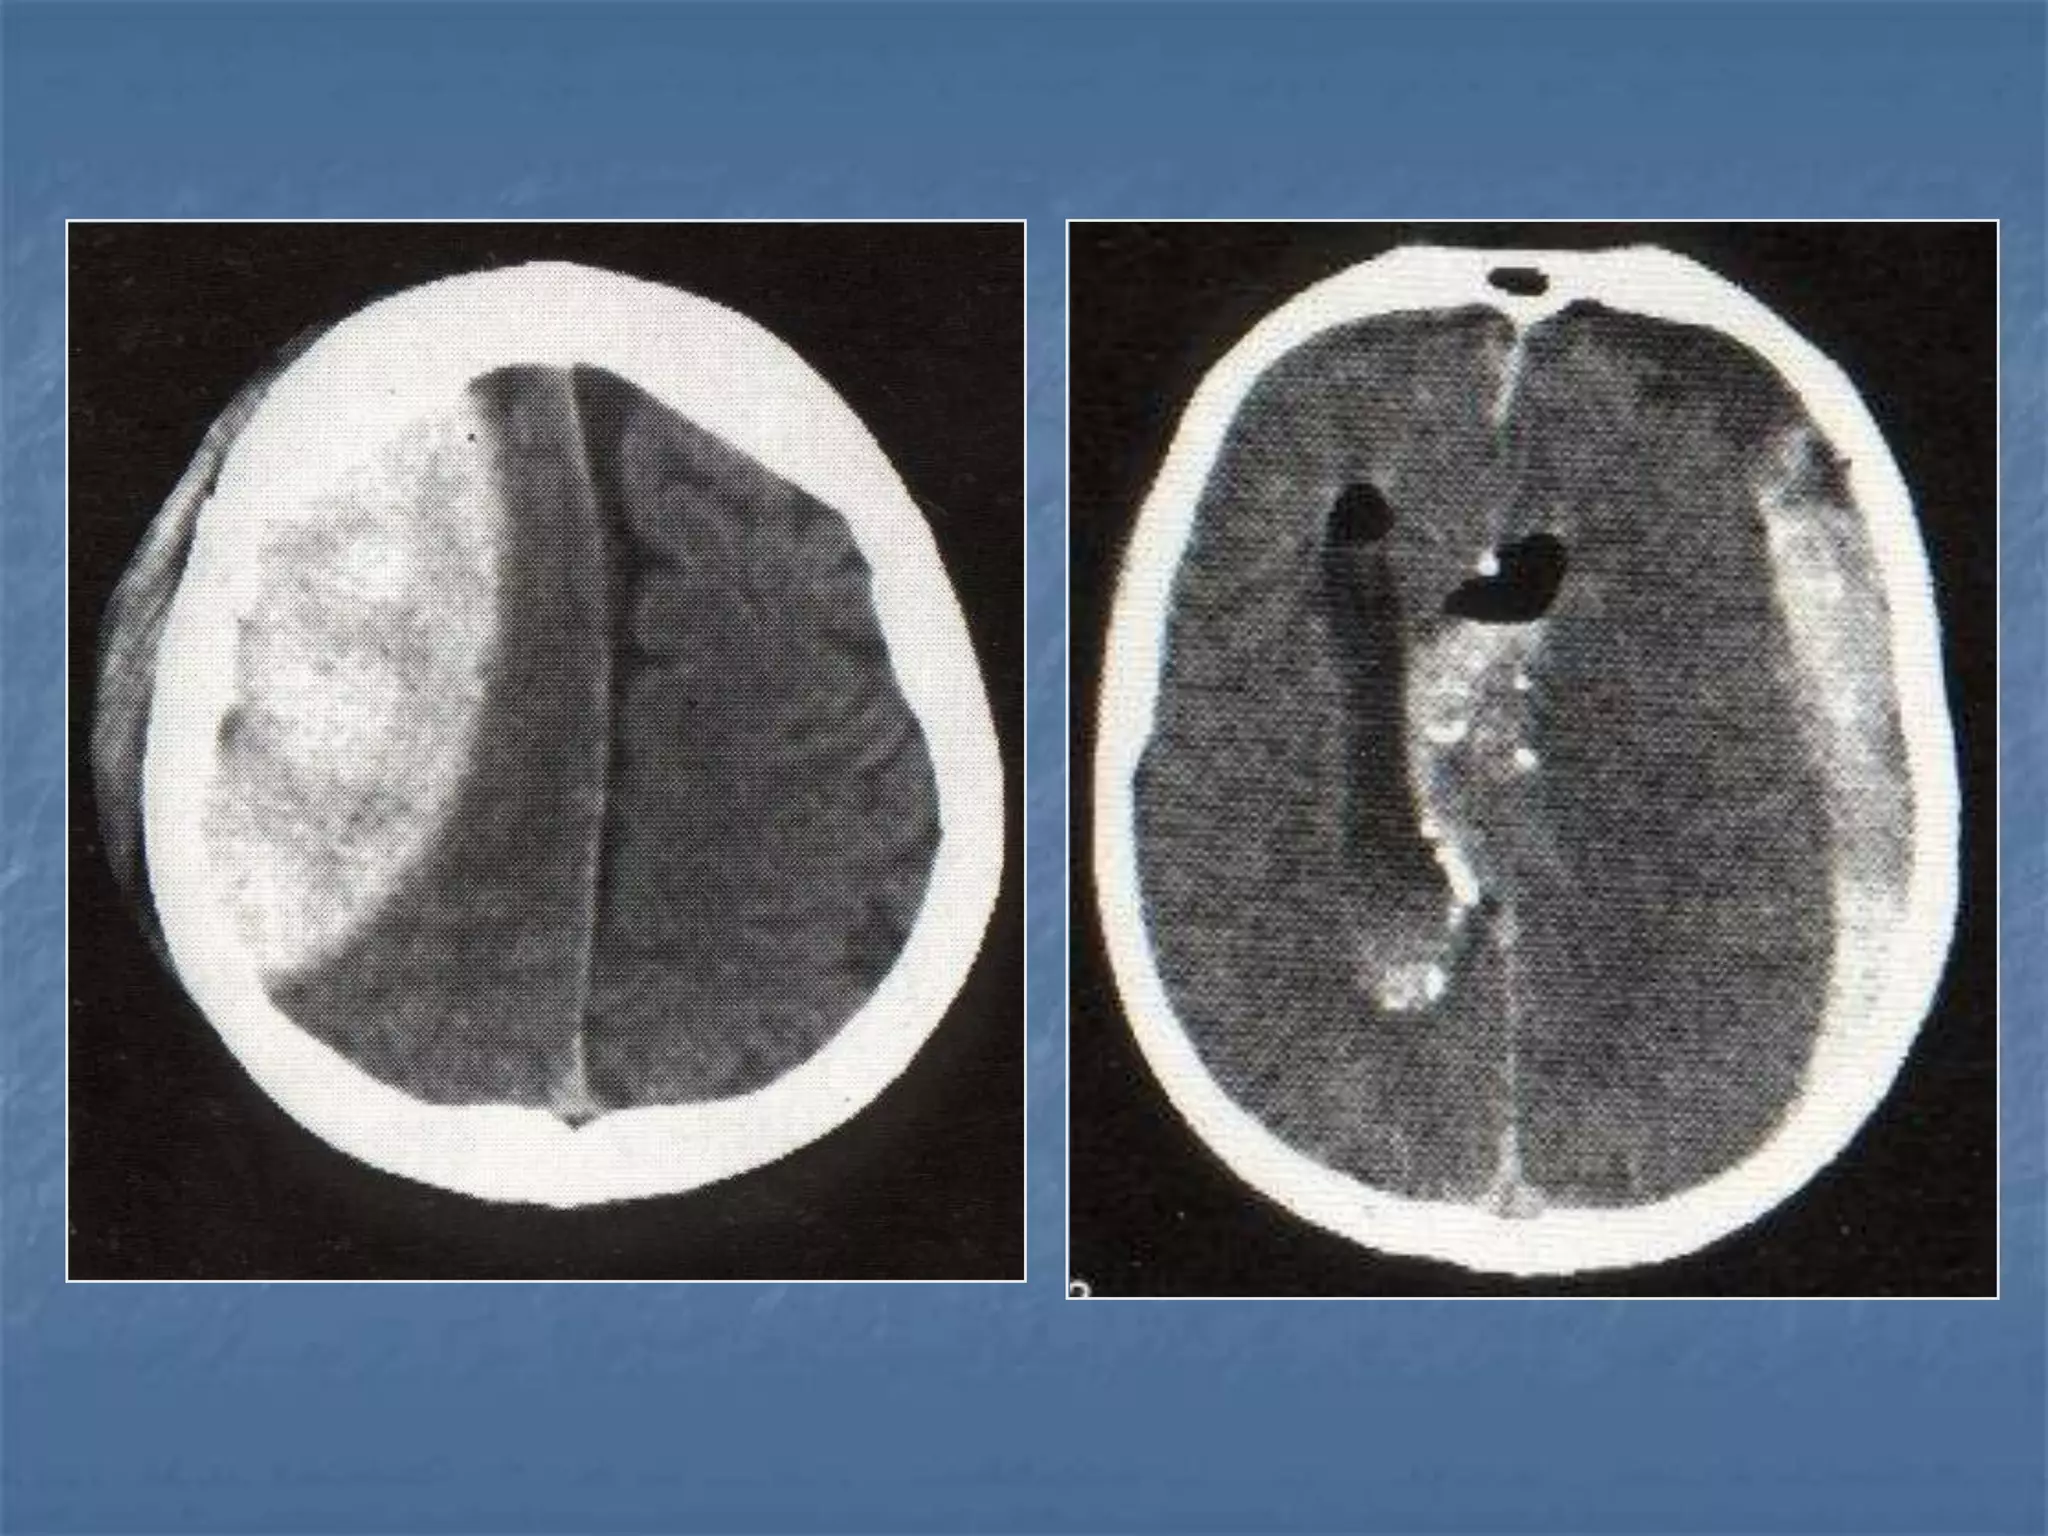

Epidural Hematoma

 An epidural hematoma is usually associated with a skull

fracture. It often occurs when an impact fractures the

calvarium. The fractured bone lacerates a dural artery or a

venous sinus. The blood from the ruptured vessel collects

between the skull and dura. On CT, the hematoma forms a

hyperdense biconvex mass. It is usually uniformly high

density but may contain hypodense foci due to active

bleeding. Since an epidural hematoma is extradural it can

cross the dural reflections unlike a subdural hematoma.

However an epidural hematoma usually does not cross

suture lines where the dura tightly adheres to the adjacent

skull

 Extradural

haematoma

 Subdural